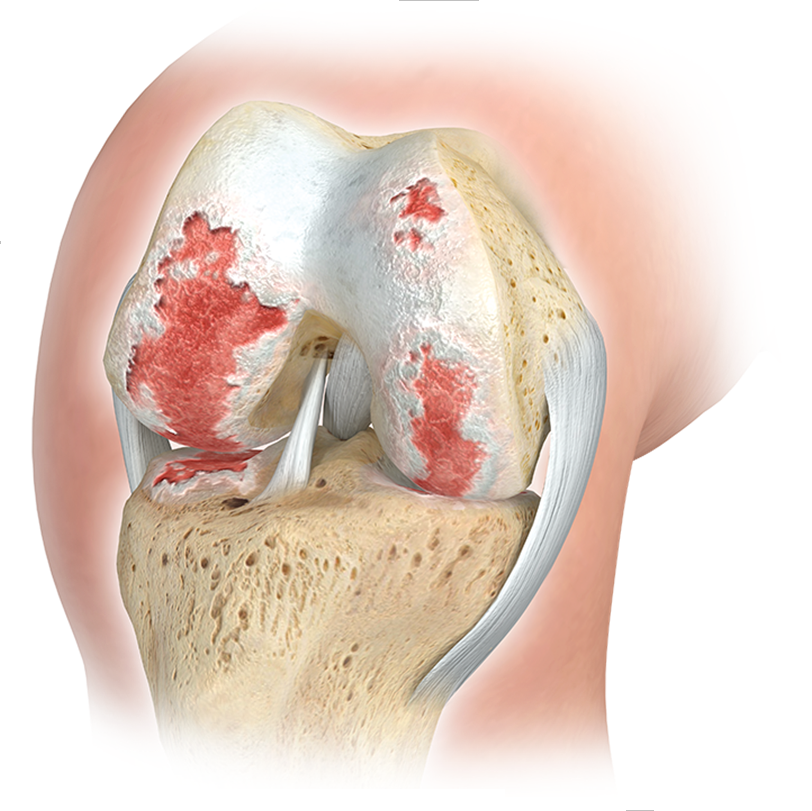

ARTHROSE DU GENOU

EN RAISON du niveau de stress élevé auquel les articulations du genou sont exposées, des signes d'usure apparaissent souvent au cours de la vie, entraînant un inconfort important et des restrictions sur la qualité de vie. Les blessures sportives précoces, les désalignements ou l’obésité favorisent considérablement cette évolution.

DANS LE CADRE DU THÉRAPIE DE L'ARTHROSE DU GENOU (arthrose du genou), DES INTERVENTIONS CHIRURGICALES PEUVENT ÉGALEMENT ÊTRE NÉCESSAIRES EN PLUS DES MESURES CONSERVATIVES :

- OPÉRATIONS DE PRÉSERVATION DES ARTICULATIONS DE L'ARTICULATION DU GENOU (CORRECTION DE POSITIONS DIVERSES ET DE VARIANTES ANATOMIQUES PAR MIRROROSCRIPTION ARTICULAIRE MINI-INVASIVE (ARTHROSCOPIE), PARFOIS ÉGALEMENT PAR OUVERTURE ARTICULAIRE (MINI-OPEN). OPÉRATIONS ENDOPROTHÉTIQUES DE L'ARTICULATION DU GENOU (REMPLACEMENT DES PARTIES ARTICULAIRES DÉTRUITES PAR IMPLANTS ARTIFICIELS EN MÉTAL ET PLASTIQUE HAUTEMENT RÉTICULÉ) .